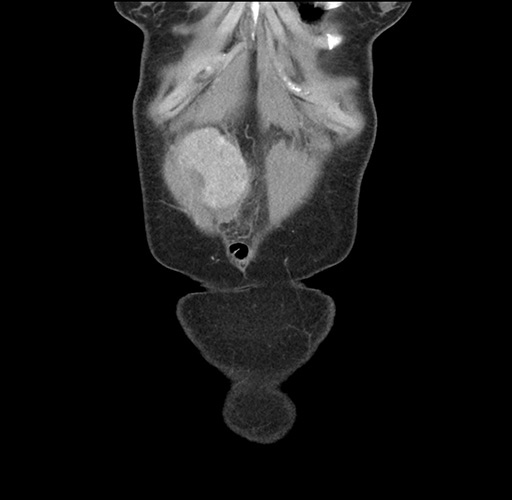

Imaging Analysis

Look through the patient's CT scan to identify any areas of concern for the necessary procedure.

Based on your CT findings, which issue(s) would give reason for "planned slowing down moment(s)" in this case?

Considering a standard left lateral sectionectomy procedure, what step(s) of the operation would you do differently in this case ?